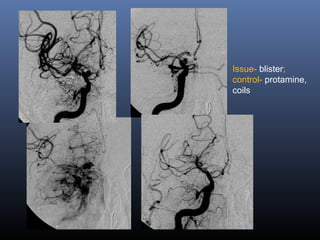

Issue- blister;

control- protamine,

coils